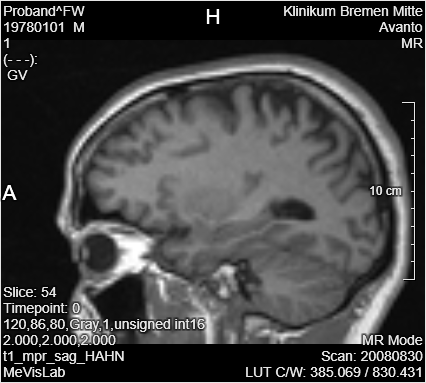

Add a LocalImage module to your workspace and select the file MRI_Head.dcm. For PyTorch, it is necessary to resample the data to a defined size. Add a Resample3D module to the LocalImage and open the panel. Change

You can use the Output Inspector to see the changes on the images after applying the resample and a swap or flip.